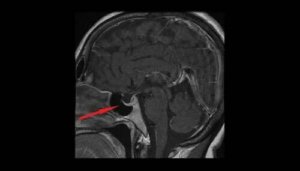

Najbardziej odpowiednie badania, które pomagają potwierdzić wstępną diagnozę, to analiza pola widzenia pacjenta, tomografia komputerowa i obrazowanie mózgu metodą rezonansu magnetycznego (MRI).